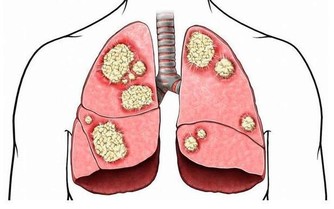

美國研究指出,擁有希臘腳的人患拇囊炎、錘狀指以及背部疾病的風險更高。

因為多數人站立或行走時,腳趾中拇指所受的重量最多,但是對於希臘腳來說,則是第二腳趾會被磨彎、磨平,進而導致腳部疾病的發生。所以擁有希臘腳的人更要注意鞋子的版型,在選擇鞋子時一定要穿起來舒適而且符合腳型,否則會對健康有更多負面的影響喔!